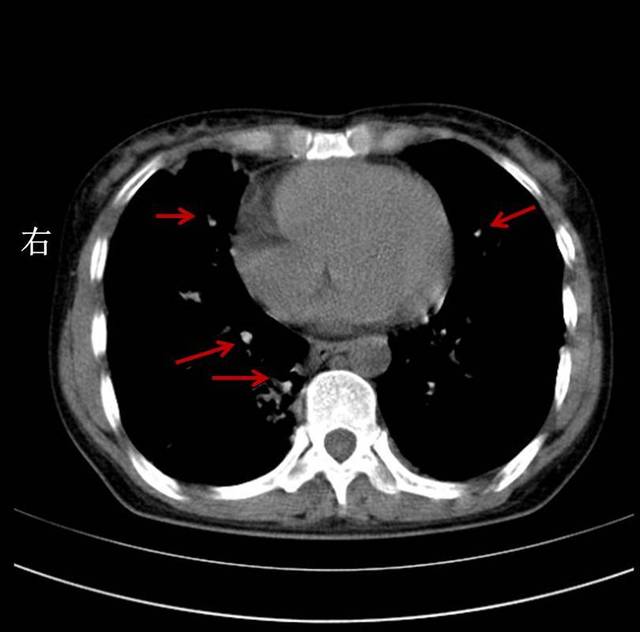

特发性肺纤维化1例丨以影识病

特发性肺纤维化影像识别一文搞定│以影识病

双肺纤维化病灶,说明病史很长.斑片状影,说明是活动性病灶.